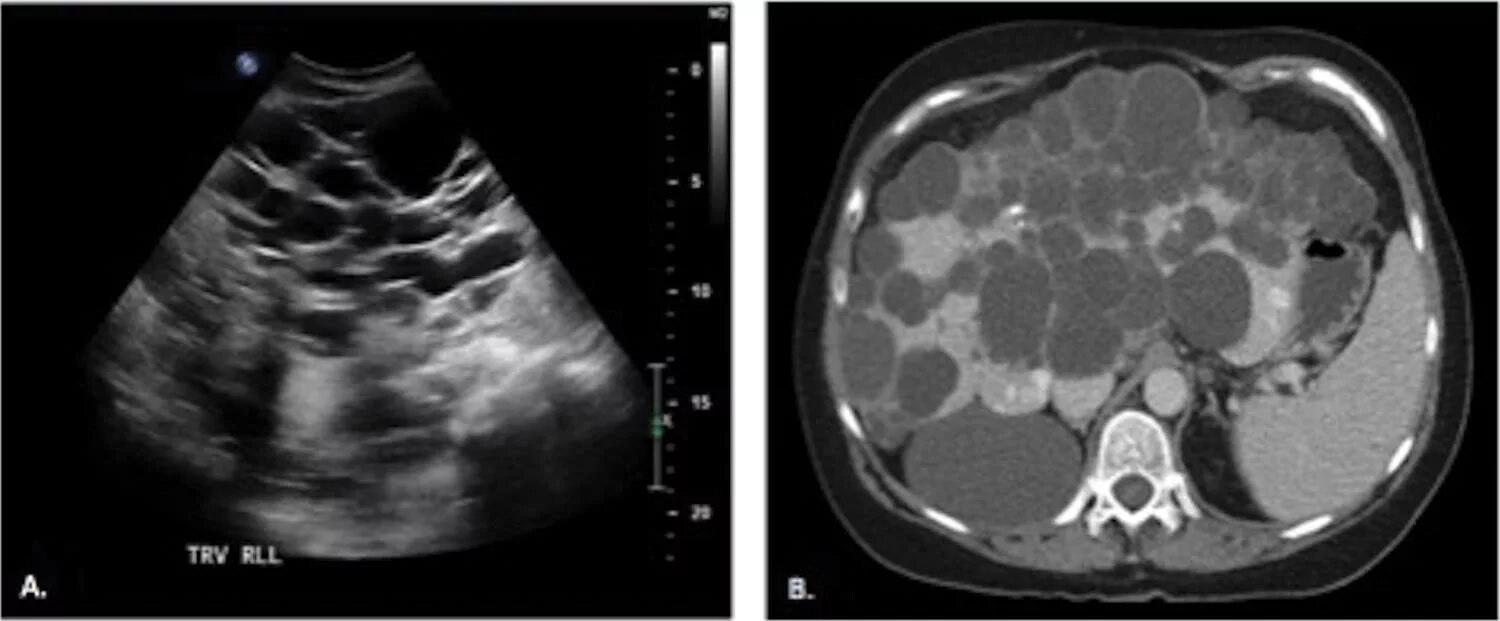

Солидные образования малый таз